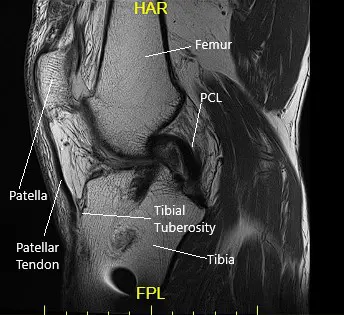

She had an MRI which showed tearing of the medial meniscus at the meniscocapsular junction and posterior horn-body junction. There was tri-compartmental cartilage loss.

Coronal MRI view of the left knee.